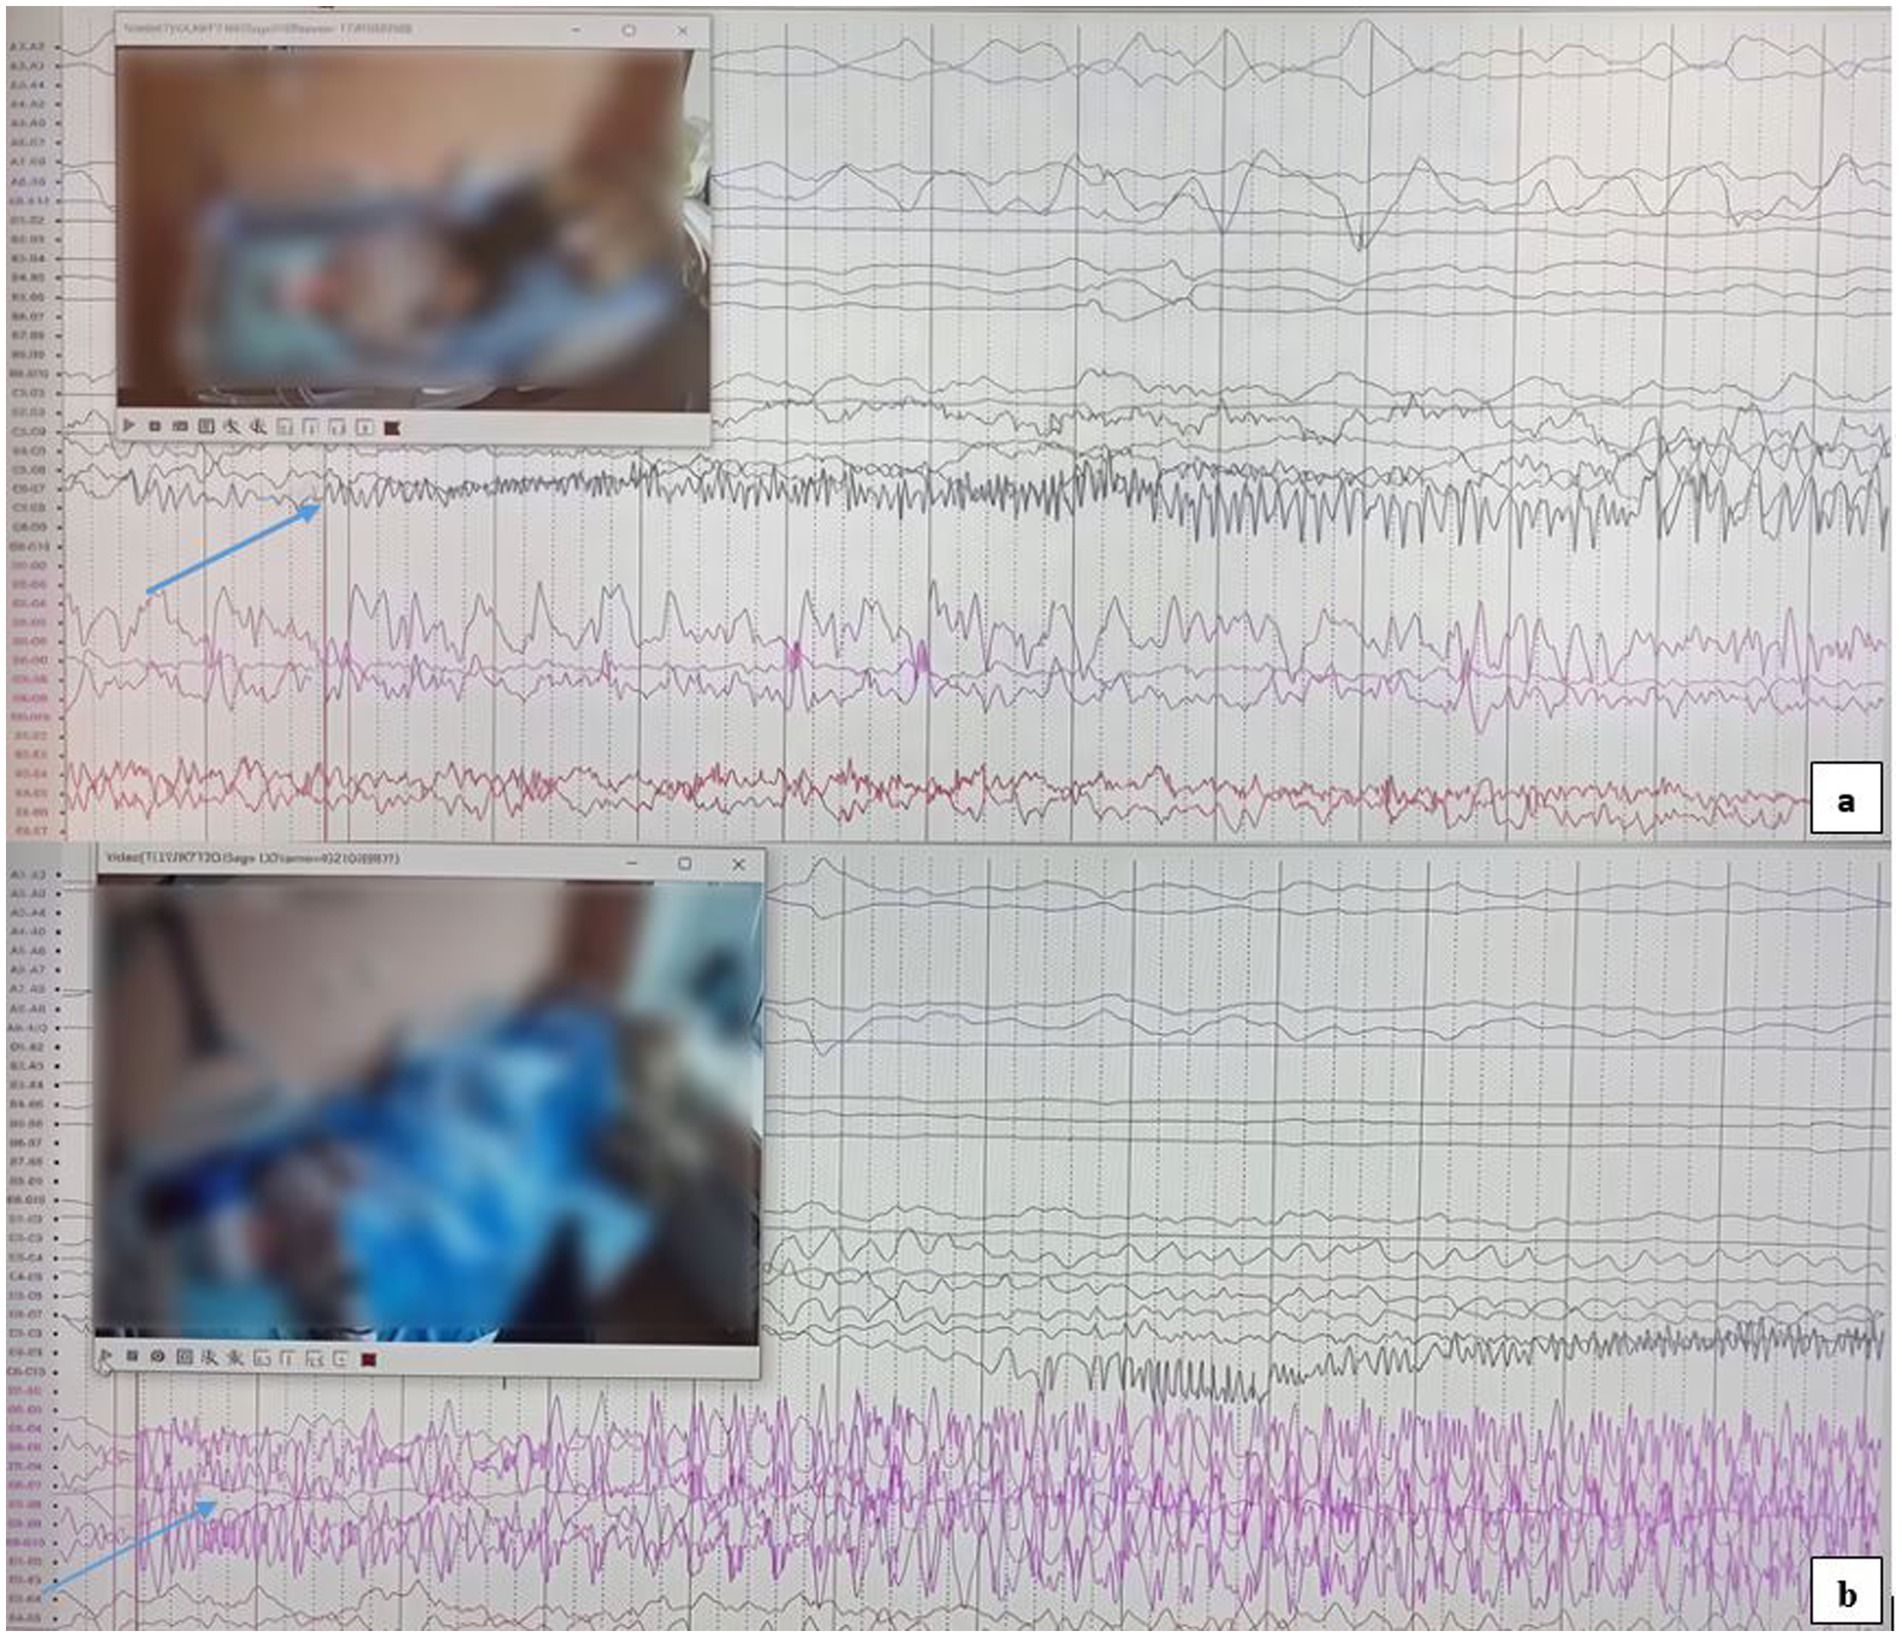

The first seizure began in the right hippocampus (Figure 3a) and subsequently propagated to the left hippocampus. It then spread to the right amygdala, likely via the anterior commissure and fornix. Finally, the discharge spread unilaterally to the left hemisphere, followed by bilateral synchronization. This rapid involvement of temporal structures is hypothesized to occur through extensive interconnections, including the commissura supracallosa, anterior commissure, and fornix.

Figure 3. (a) Epileptic seizure activity originating from the right hippocampus, as indicated by the arrow. (b) The SEEG recording shows epileptic seizure activity originating from the left hippocampus, with the onset clearly marked by the arrow.

The second seizure, originating in the left hippocampus (Figure 3b), was rapidly followed by bilateral synchronization. The swift propagation to the contralateral hemisphere suggests a short and efficient pathway for epileptic activity spread, likely involving the corpus callosum and thalamocortical connections. This phenomenon was ultimately characterized as an independent focus.

The third seizure was recorded in the left orbitofrontal region, definitively indicating the presence of multifocal epilepsy. This finding, in addition to the bilateral temporal seizure onsets, significantly reduces the likelihood of successful focal resection.